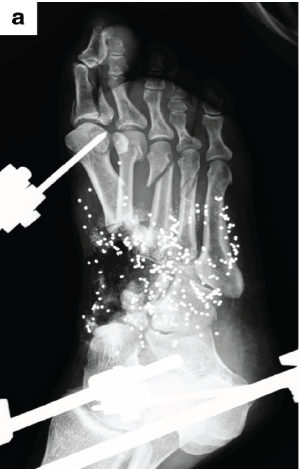

Reconstructive Surgery for Foot Ectrodactyly in an Adolescent Patient: A Case Report

Centenarro Jose S Meceda , Adrian Joseph C Tablante , Emiliano B Tablante ………………………………p.205-210